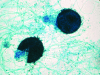

Scedosporium spp. are increasingly recognized as causes of resistant life-threatening infections in immunocompromised patients. Scedosporium spp. also cause a wide spectrum of conditions, including mycetoma, saprobic involvement and colonization of the airways, sinopulmonary infections, extrapulmonary localized infections, and disseminated infections. Invasive scedosporium infections are also associated with central nervous infection following near-drowning accidents. The most common sites of infection are the lungs, sinuses, bones, joints, eyes, and brain. Scedosporium apiospermum and Scedosporium prolificans are the two principal medically important species of this genus. Pseudallescheria boydii, the teleomorph of S. apiospermum, is recognized by the presence of cleistothecia. Recent advances in molecular taxonomy have advanced the understanding of the genus Scedosporium and have demonstrated a wider range of species than heretofore recognized. Studies of the pathogenesis of and immune response to Scedosporium spp. underscore the importance of innate host defenses in protection against these organisms. Microbiological diagnosis of Scedosporium spp. currently depends upon culture and morphological characterization. Molecular tools for clinical microbiological detection of Scedosporium spp. are currently investigational. Infections caused by S. apiospermum and P. boydii in patients and animals may respond to antifungal triazoles. By comparison, infections caused by S. prolificans seldom respond to medical therapy alone. Surgery and reversal of immunosuppression may be the only effective therapeutic options for infections caused by S. prolificans.